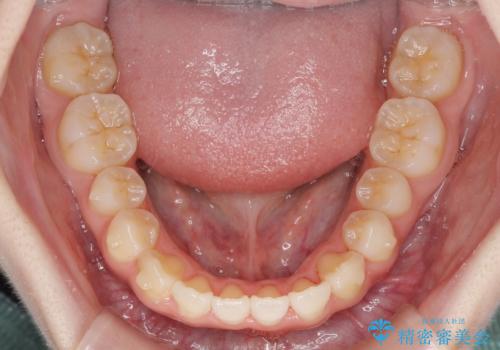

- 前歯の捻れと、ちょっとした出っ張りを気にして来院された患者様です。

歯と歯の間を削る(IPR)ことでデコボコを解消し、インビザラインで整えることとしました。

インビザライン治療特有の奥歯が接触しない時期が続き、当初予定よりも期間がかかりましたが、最終的には安定した咬み合わせと、整った前歯になりました。